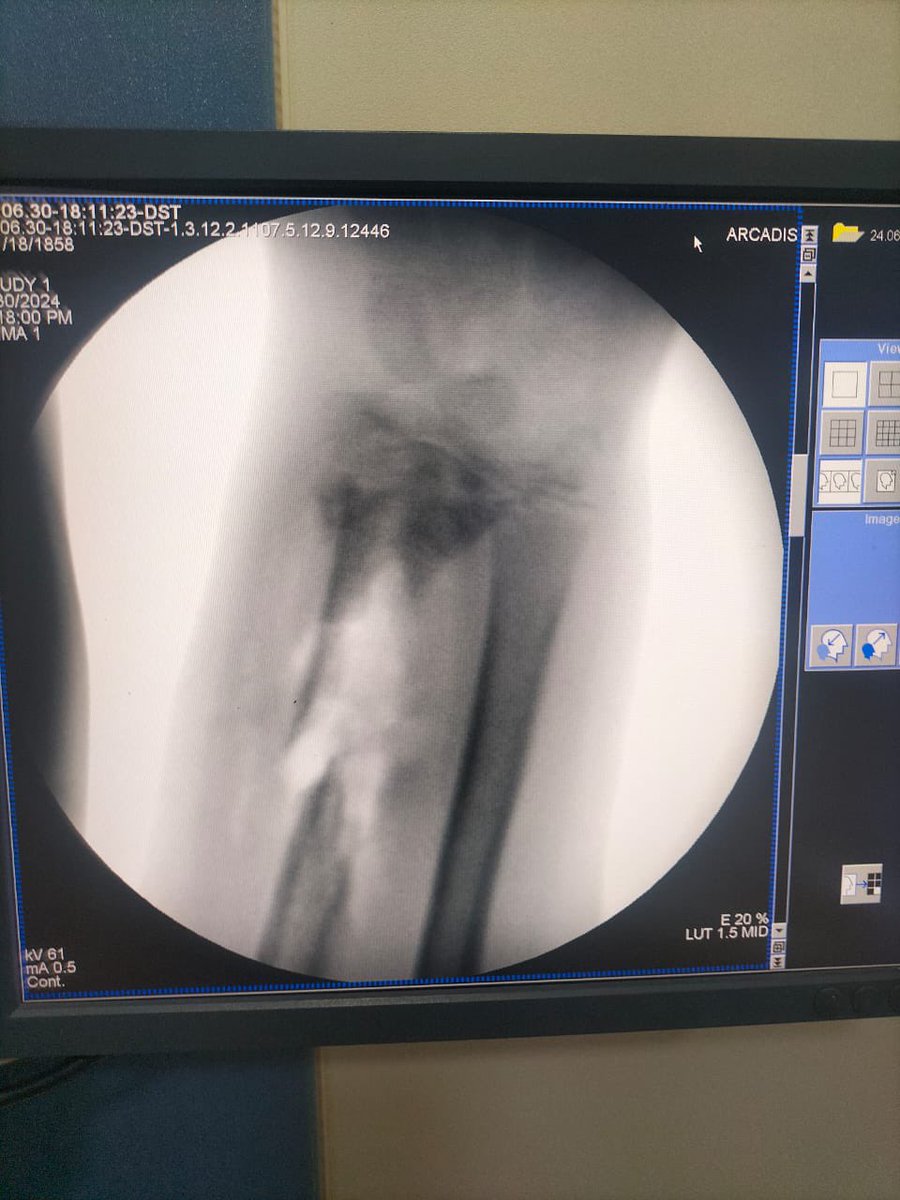

تم استئصال العظام الميتة و تركيب اسمنت طبي مؤقت لحين التأكد من انتهاء الصديد ثم عمل ترقيع للعظم.